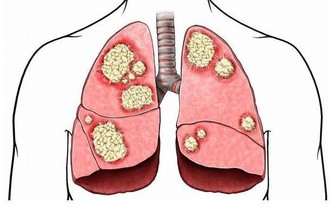

5.指甲發青指甲發青可能代表你的身體沒有得到足夠的氧氣。

心臟負責將身體所需的氧氣經由血液送達全身,指甲發青很可能是你的心臟出了問題。